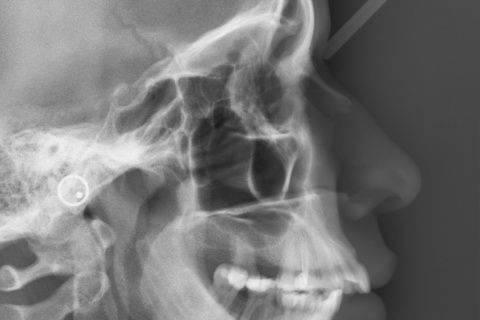

Foto Inicial.

Resumo

Paciente do sexo feminino

Primeira opção sugerida foi Cirurgia Ortognática, porém paciente não aprovou.

Foi sugerido uma conduta de distalização superior(alertamos a pacinte quando a mudança do angulo naso-labial) com uso de M.P.O. com poucas chances de sucesso.